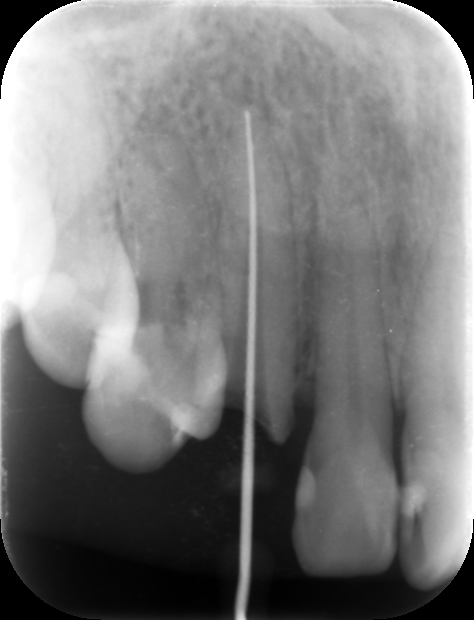

初診時レントゲン。右の鼻の付け根を押したときの痛みを主訴に来院。右側上顎犬歯は神経を取ってあり、補綴物(被せ物)が装着してある(白いレントゲン不透過像)。根管治療が不十分で、歯根の先端に骨の吸収を疑わせる黒いレントゲン透過像を認める(根尖病巣)。

ファイル(治療用の細い器具)を歯根の内部に挿入して、根管の長さと方向を確認しているところ。根尖までファイルが届いているのが分かる。